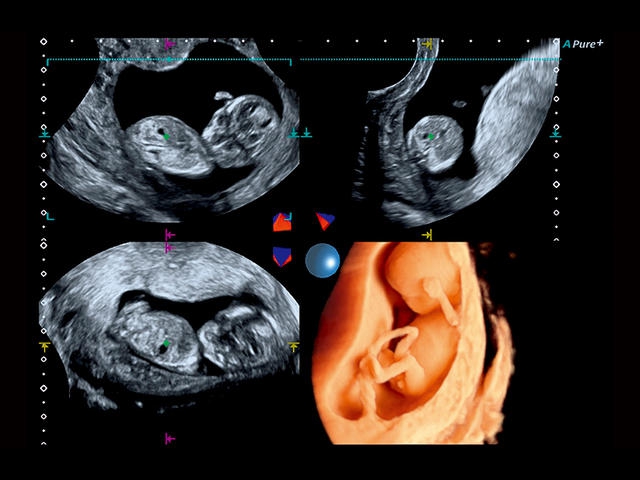

Aplio 500 – ультразвуковой сканер премиум класса, сочетающий в себе быстродействие диагностики и отличное качество визуализации. Более 30 датчиков на выбор, в т.ч. матричные, монокристаллические, 4D, эндоскопические для любых типов исследований. Ультразвуковой сканер позволяет изучать анатомические структуры в высоком разрешении.

Обновленная версия легендарного УЗ-сканера. Стационарный аппарат экспертного класса Aplio 500 Toshiba NEW, визуализирует анатомические структуры в высоком разрешении. Модель позволяет выявить микрокальцификаты, новообразования, нарушения в работе сердца, сосудов и мышц. Присутствует функция виртуальной эндоскопии, 4D-сканирования, эластометрии тканей, УЗИ с контрастированием. За повышение качества изображения отвечают технологии ApliPure и Superb Microvascular Imaging. Первая задействует возможности пространственного и частотного кодирования, формирует цельный визуальный ряд с сохранением клинических маркеров. Вторая улучшает отображение микрососудистого русла, используя доплеровский эффект. Модель оснащена 21-дюймовым монитором, имеет 4 активных порта. Возможно подключение педиатрических, интраоперационных, лапароскопических и чреспищеводных датчиков.